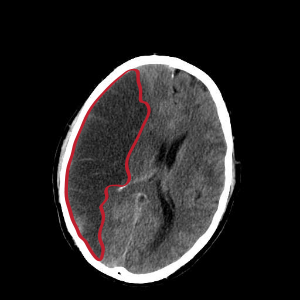

뇌경색 초기증상 - 시야 장애

가파르게 물체가 잘 보이지 않거나 두 개로 나누어서 보이는 경우가 생깁니다. 한쪽 눈만 보이거나 양쪽 눈에 이상이 생기기도 하더라고요. 한 접시에 두 가지 음식이 나누어서 담겨 있어도 한쪽만 보이며 다른 쪽의 음식은 인지하지 못하더라고요.